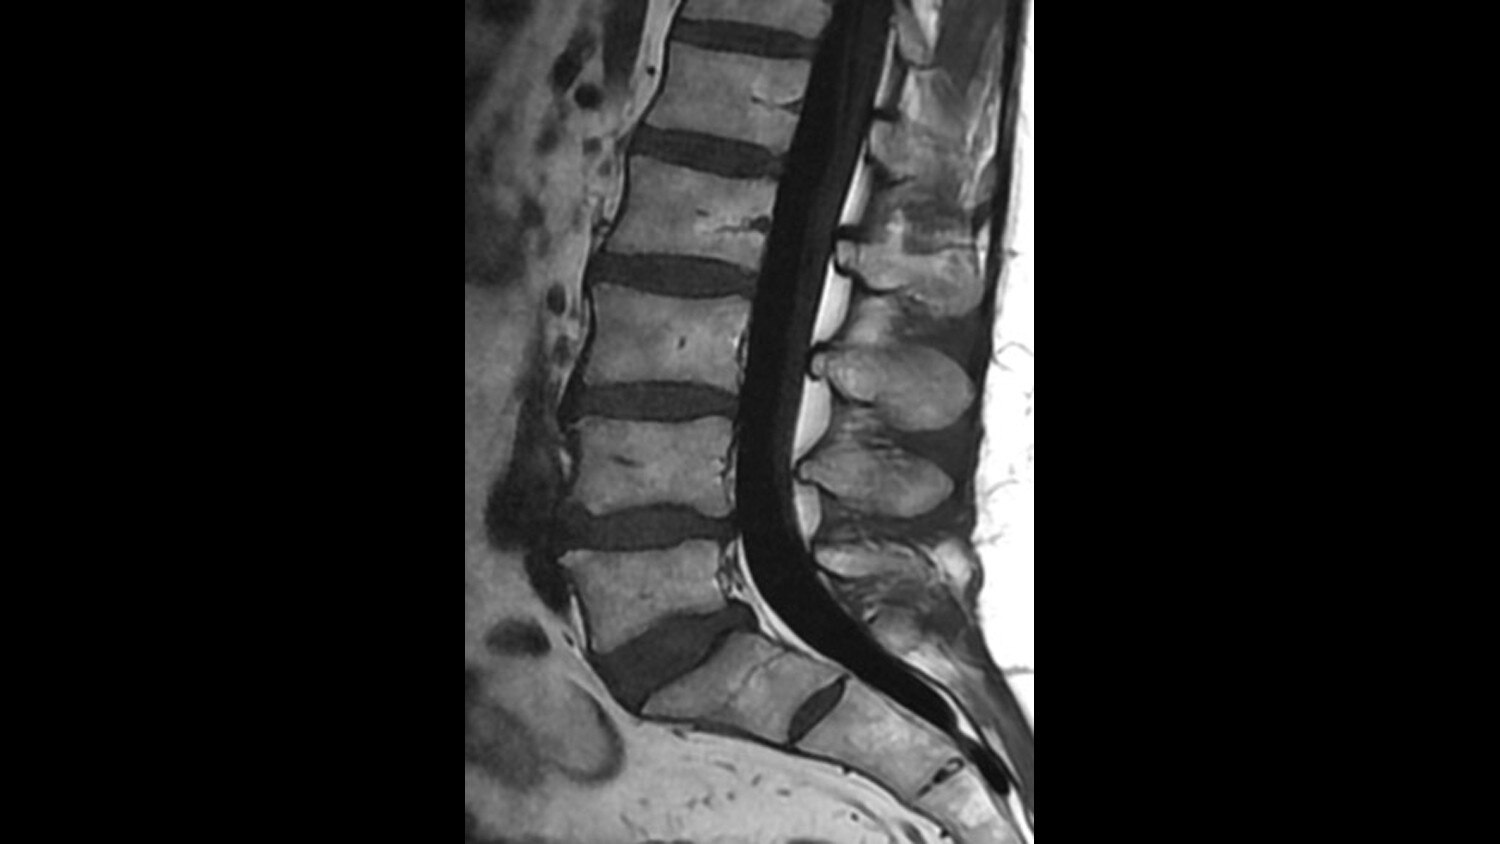

For the first time ever in the industry, you can generate multiple image contrasts in a single MRI scan including T1, T2, STIR, T1 FLAIR, T2 FLAIR* and PD contrasts of the brain in a single acquisition.

One scan that can do the work of many, with images acquired in as little as half the time to acquire separate sequences, fully integrated in a seamless workflow.